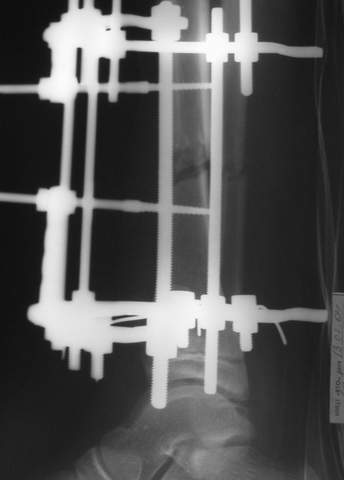

2

3a

3b

3c

В аттачте № 3 - один из примеров полукольцевого аппарат...

Это уже я баловался.

Итог? Работы больше (по времени и

интраоп "подгонке"), срастается также, а особого преимущества по сравнению с

"чиста" кольцевым (вес, удобство ношения и пр.) - я, по крайней мере,

не нашел.

Теперь не балуюсь.

Может быть зря?